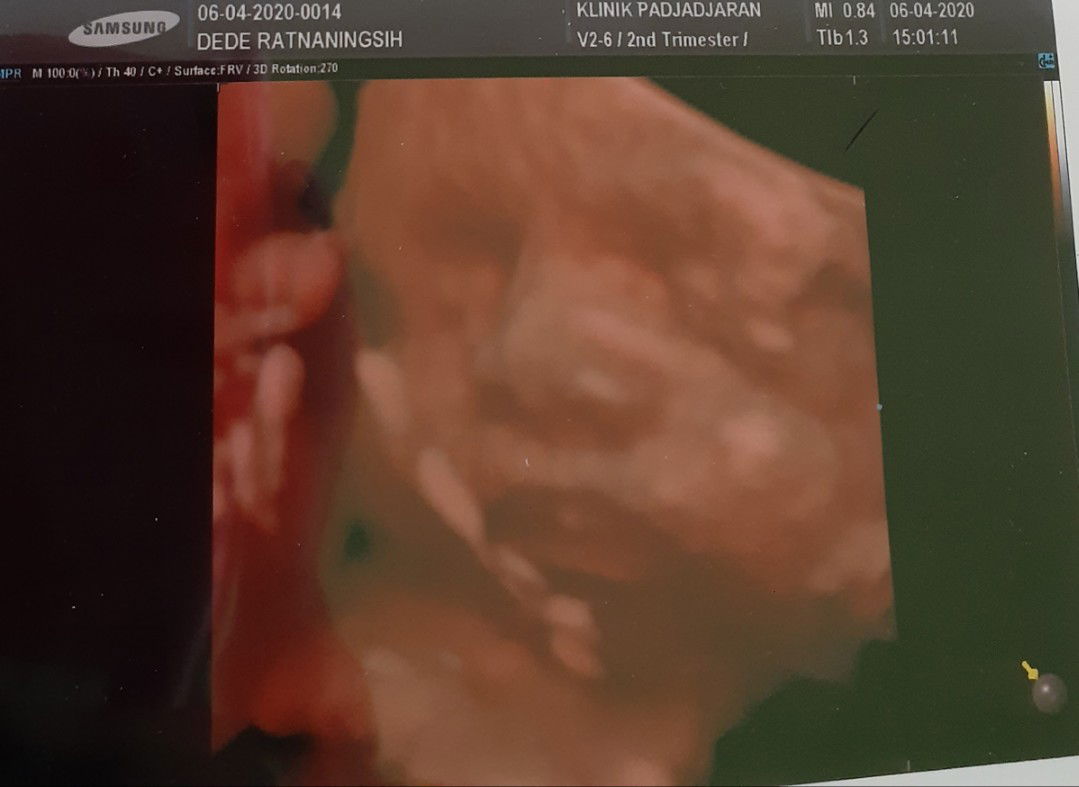

Tadi saya usg 4d...alhamdulillah baby boy lagi,usia kandungan saya skrg 28wk.. tapi dokter bilang posisi dd masih melintang,terus plasenta letak rendah,ada satu lilitan tali pusat juga d leher dd..aga was2 dan kefikiran jg,,katanya klo ampe ga berubah ga bisa lahir normal..naudzubillah..mdh2an bln dpn udh bagus posisi dd nya? mohon doa nya ya buat semuanya?